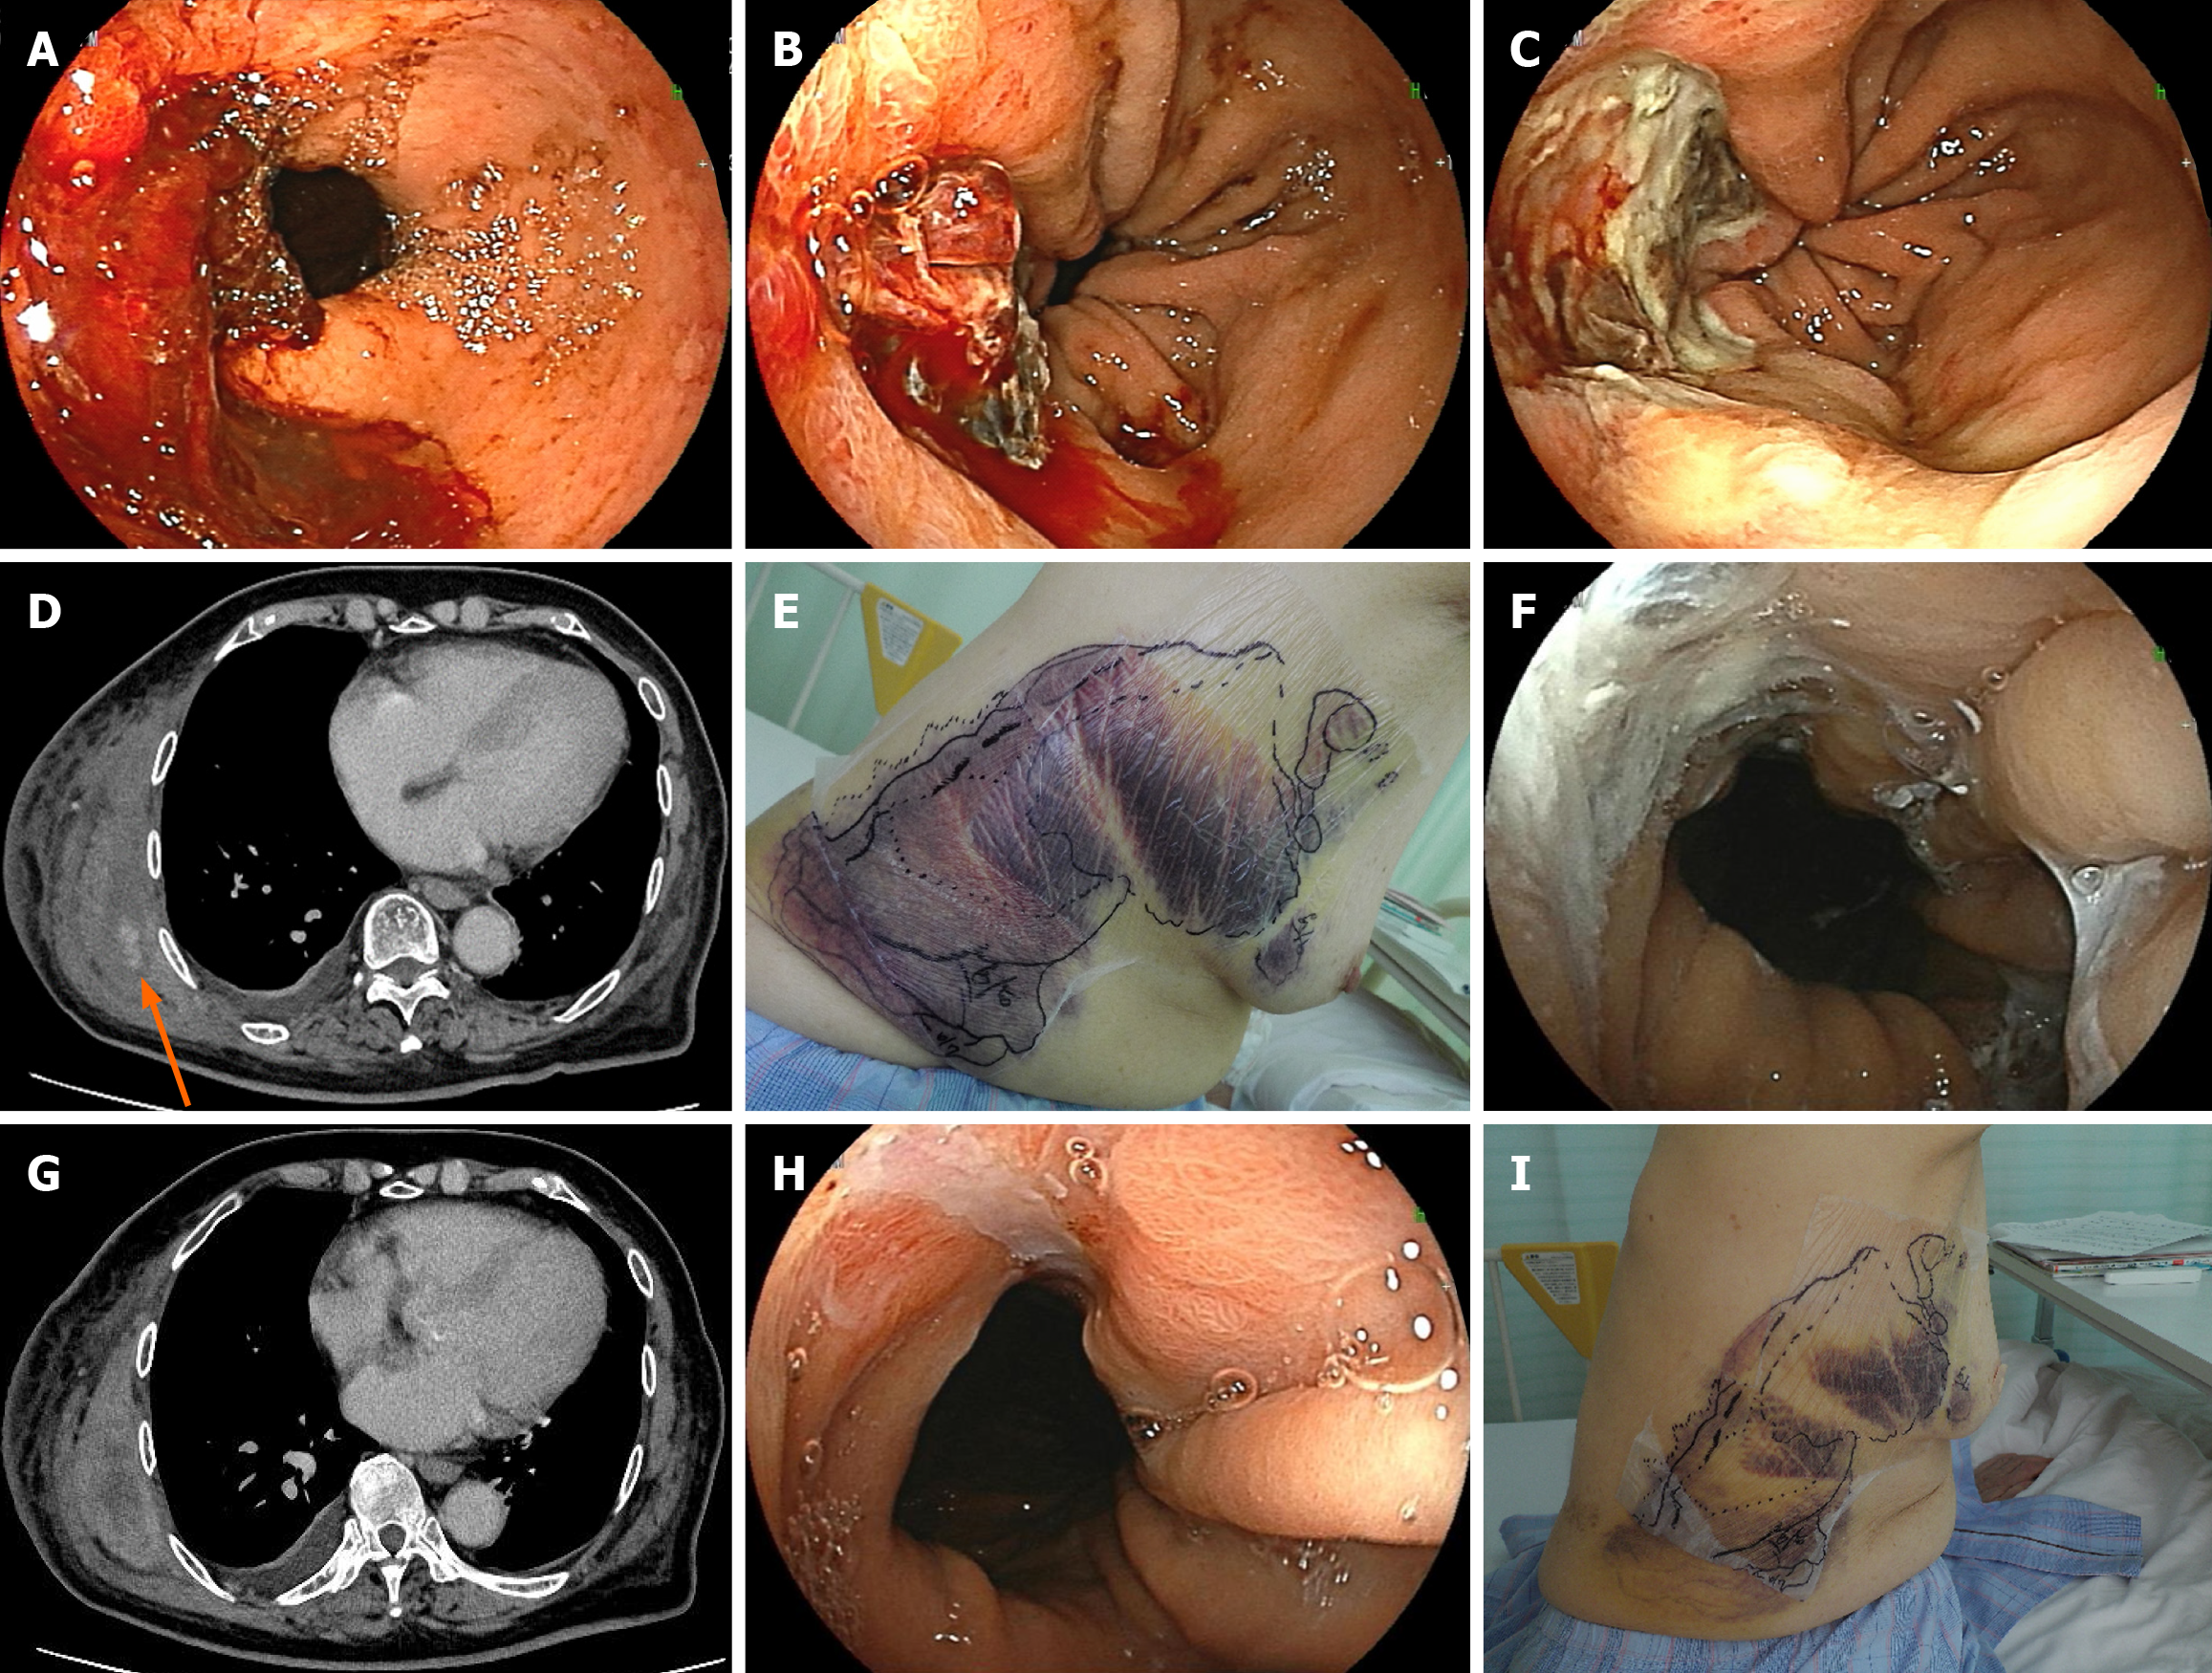

Figure 2 Management of refractory hemorrhage with a novel hemostatic agent: From diagnosis to hemostasis.

A and B: Esophageal endo scopic findings at the time of admission. Before treatment, oozing hemorrhage was observed from an ulcer within the hiatal hernia (A); After treatment, clipping was attempted to stop the bleeding, but new bleeding occurred from the clipped area (B); C: Esophageal endoscopic findings of changes in ulcer lesions: A single dose of the hemostatic agent (Byclot®) resulted in complete hemostasis; D: Computed tomography findings of the intramuscular hematoma: A large intramuscular hematoma was present in the right chest, accompanied by arterial extravasation (indicated by the orange arrow); E: Subcutaneous bleeding finding: Widespread subcutaneous bleeding was observed in the right chest; F: Esophageal endoscopic findings of changes in ulcer lesions: Two weeks after the administration of Byclot® (around the same time as D and E), the esophageal ulcer remained hemostatic; G: Computed tomography findings of the intramuscular hematoma: Hemostasis was confirmed 5 days after the administration of a mixture of factors VIIa and X (Byclot®); H: Esophageal endoscopic findings of changes in ulcer lesions: One week after emicizumab administration, the esophageal ulcer showed a marked tendency to heal; I: Subcutaneous bleeding finding: One week after emicizumab administration, the subcutaneous bleeding resolved rapidly.